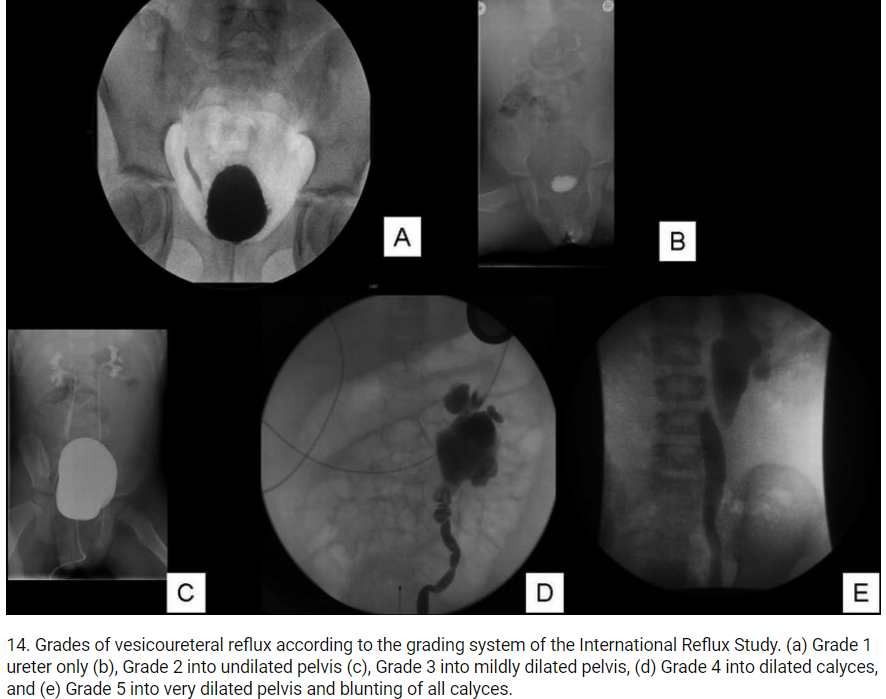

11B/ VCUG findings and grading

⚡️Findings: Retrograde reflux of the contrast into the ureters during micturition is diagnostic of VUR.

⚡️Grading: Divided in to 5 grades based on the severity of VUR on VCUG Image

Image